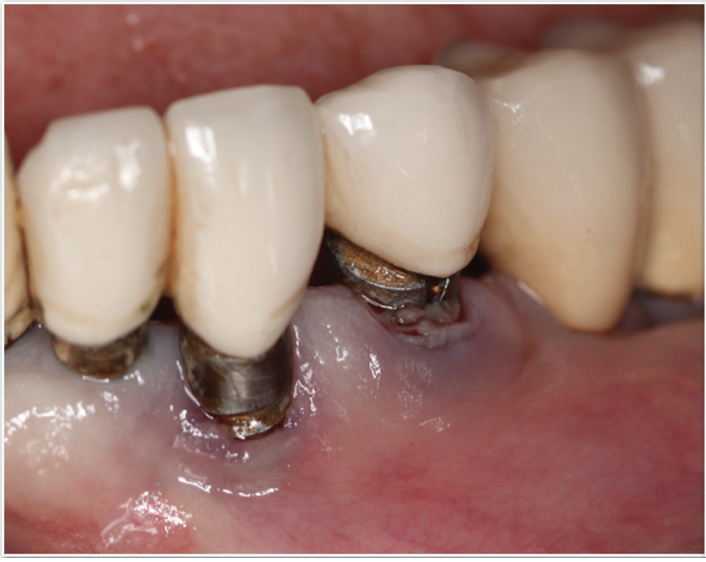

Fig 3 and Fig 4. Pre- (Fig 3) and post-treatment (Fig 4) photographs of a patient who received free gingival grafting at implant sites Nos. 21 and 22. Note the increased amount of keratinized tissue at the areas postoperatively (Fig 4). The patient was placed on 3-month supportive peri-implant care post-surgery and reported increased comfort during her home care regimen.

Figure 3

Figure 4